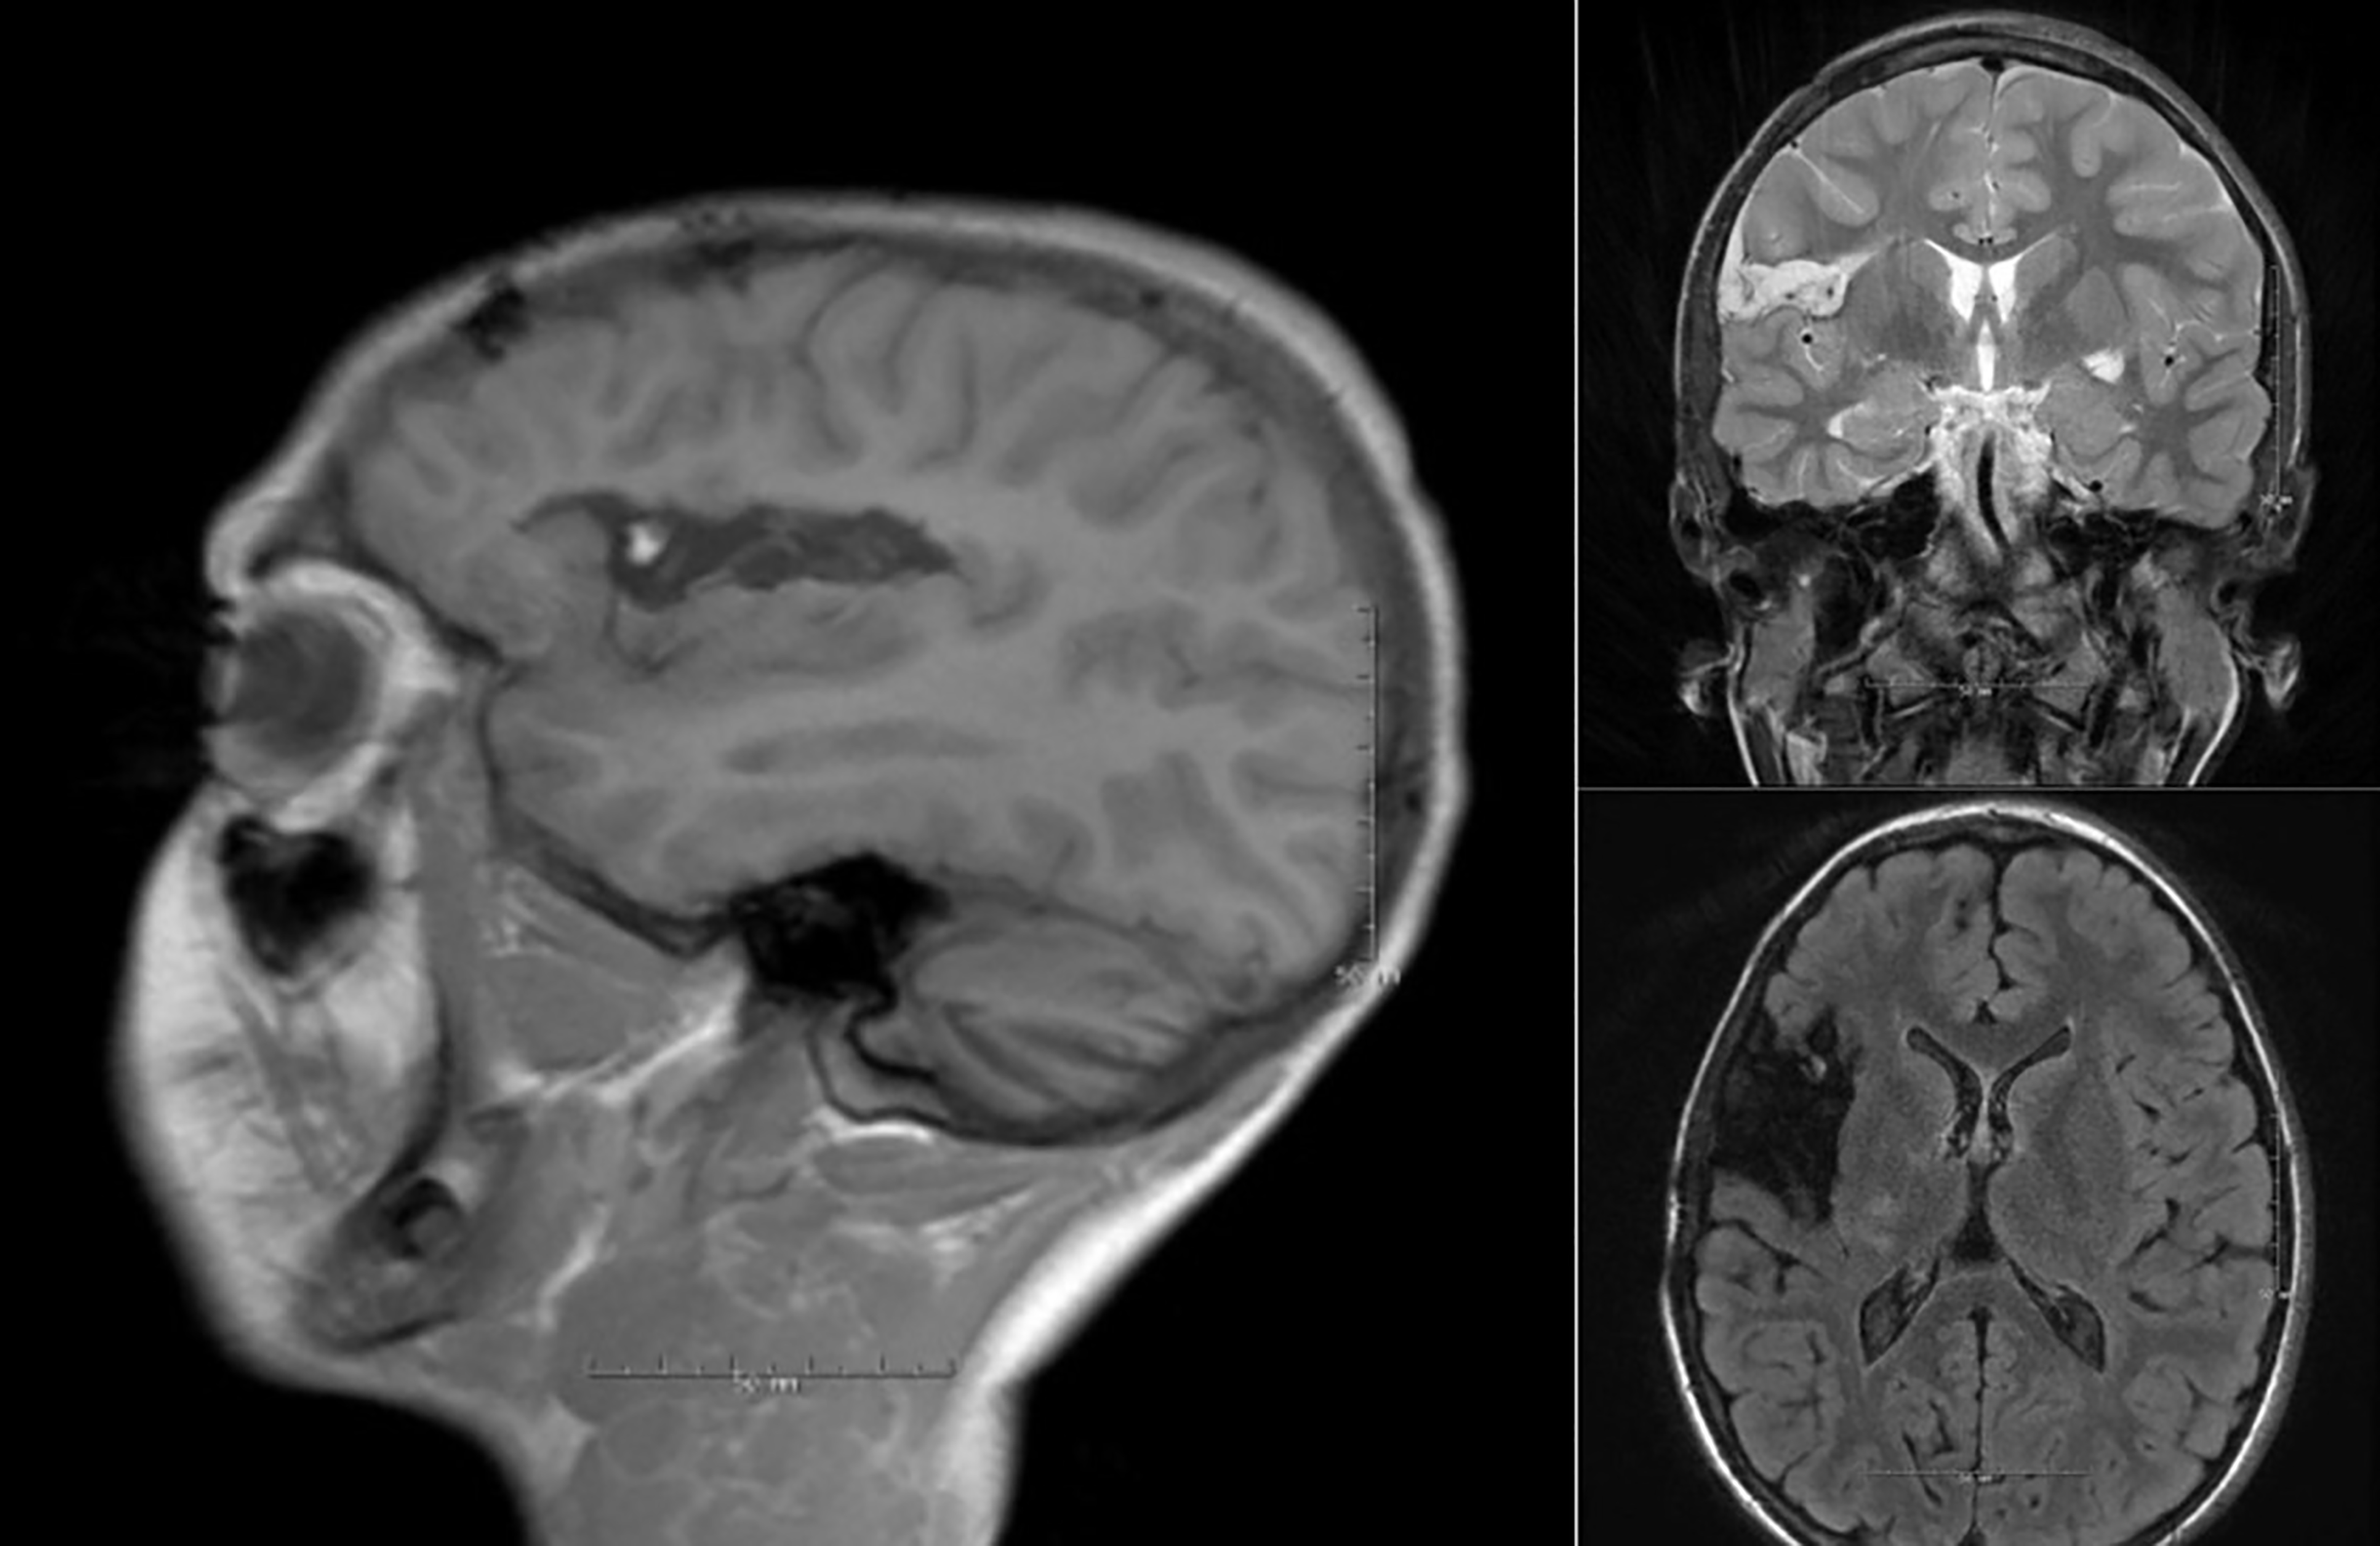

Surgical resection remains the first-line treatment for patients with DRE (Fig. 2). Initial attempts at insular resection in the 1950s and 1960s were abandoned due to high morbidity and low rates of seizure freedom [34, 35]. However, advancements in microsurgical techniques and neuroimaging have since led to improved outcomes and lower morbidity rates.

Fig. 2.

Post operative MRI after dorsal insula resection due to medically refractory epilepsy. The resection resulted in complete arrest of the epileptic activity. MRI, magnetic resonance imaging.